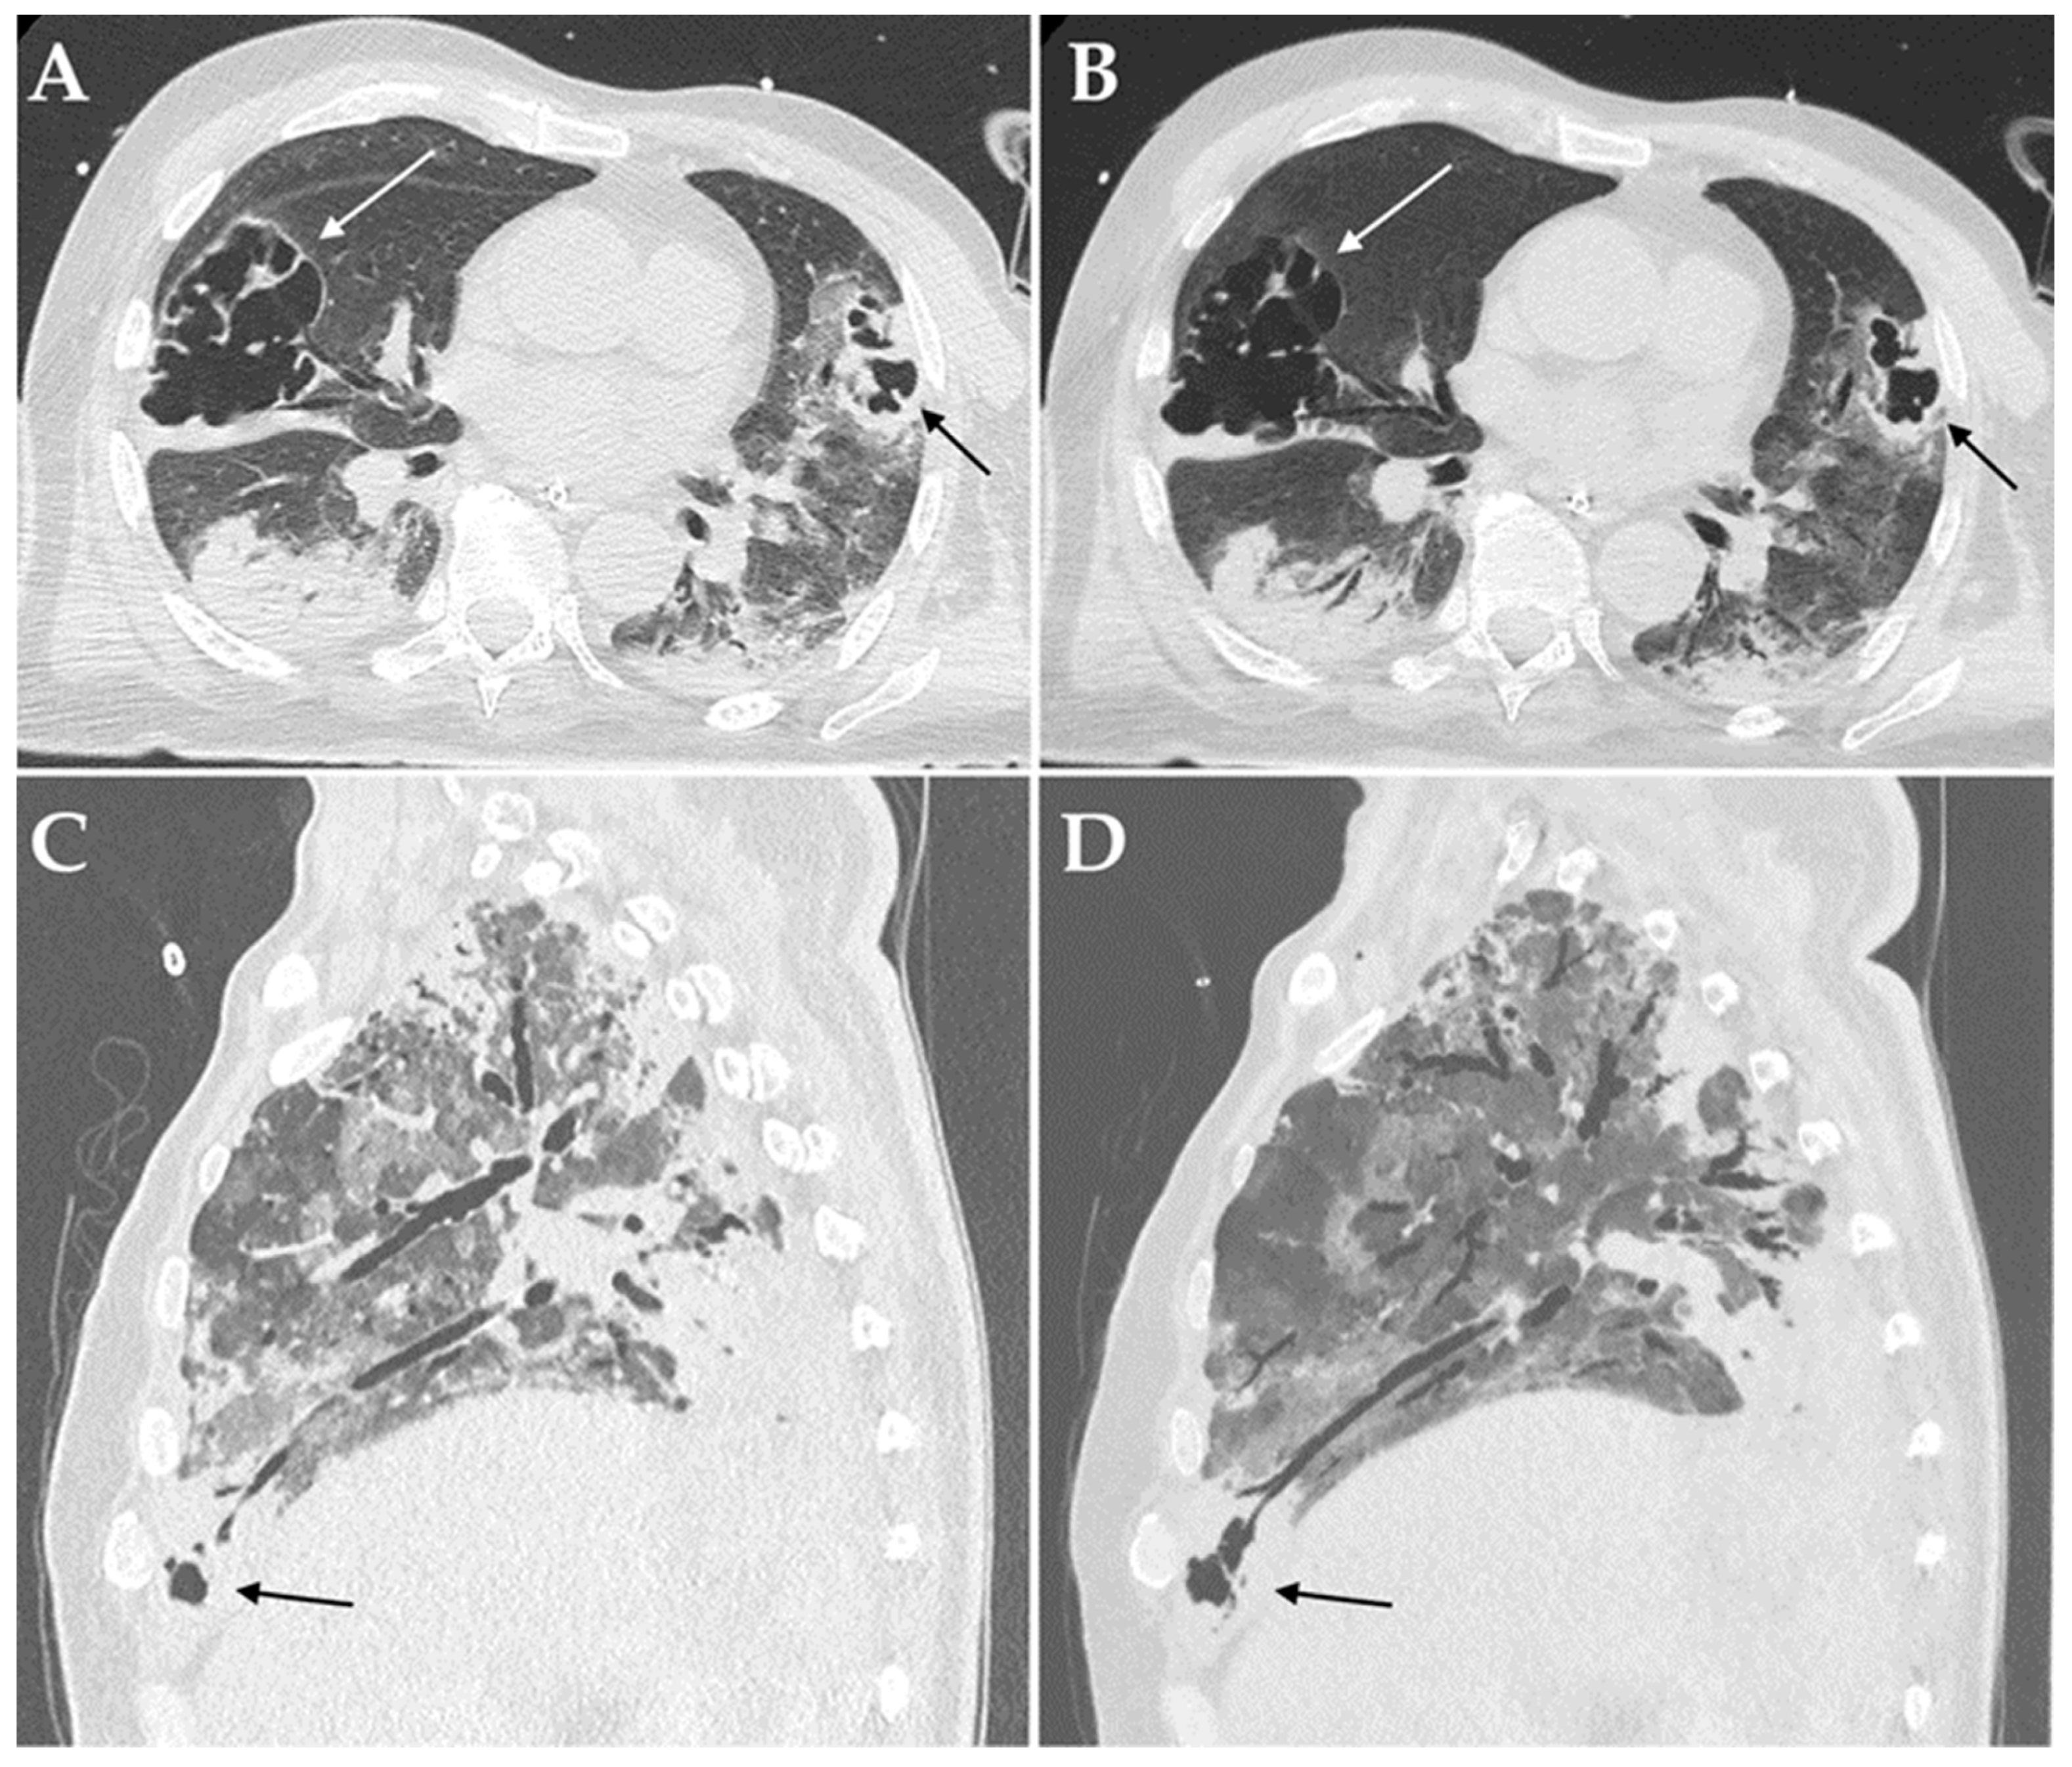

| Cavitations | 16 (16.8%) | 15 (23.8%) | 1 (3.1%) | 0.010 |

| Bronchiectasis | 17 (17.9%) | 16 (25.4%) | 1 (3.1%) | 0.009 |

| Cavitations | 16 (30.8%) | 0 (0.0%) | 0.052 | 14 (73.7%) | 2 (6.1%) | <0.001 |

| Bronchiectasis | 16 (30.8%) | 0 (0.0%) | 0.052 | 15 (78.9%) | 1 (3.0%) | <0.001 |